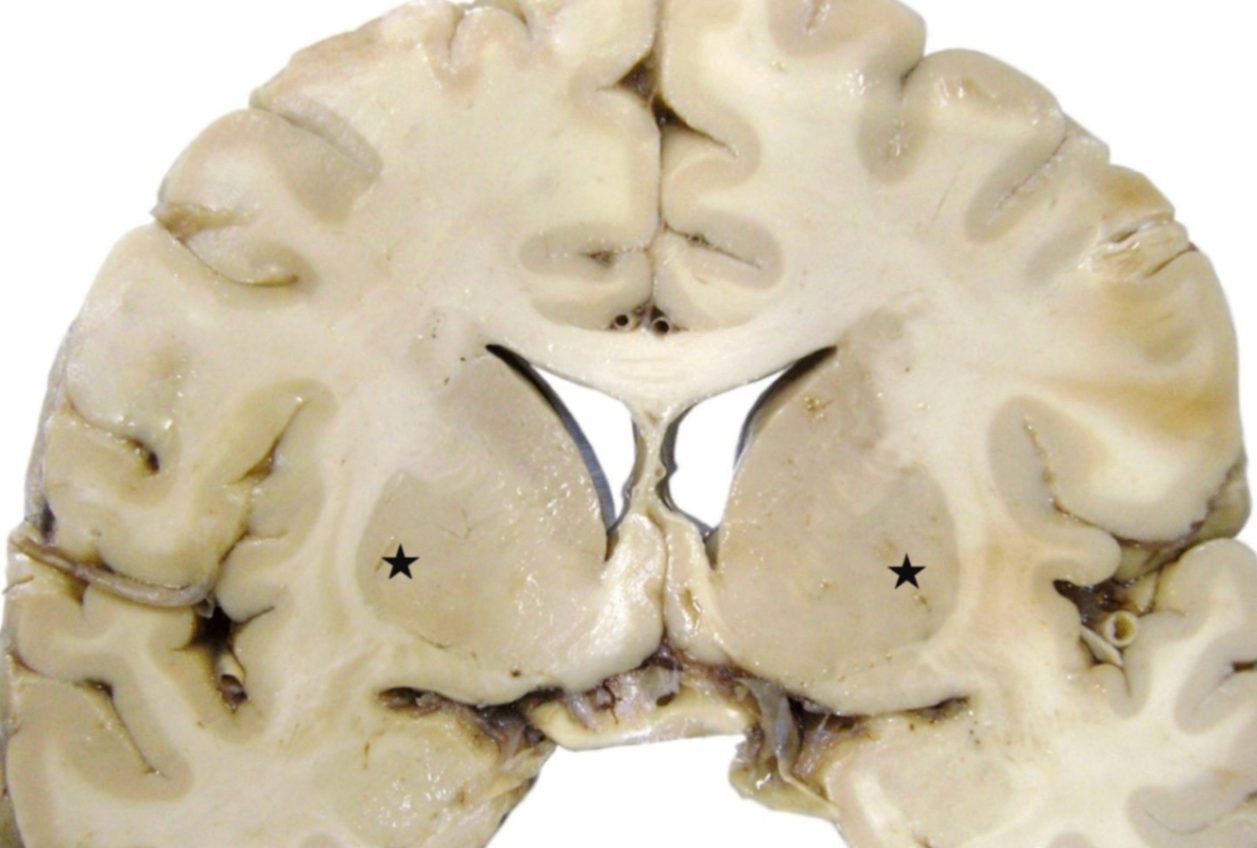

뇌 관상면에서 별 모양으로 지시된 회색질 부위는?

• 표시된 부위는 조가비핵(putamen)에 해당한다. 안쪽의 창백핵(globus pallidus)과 헷갈리지 않도록 주의해야 한다.